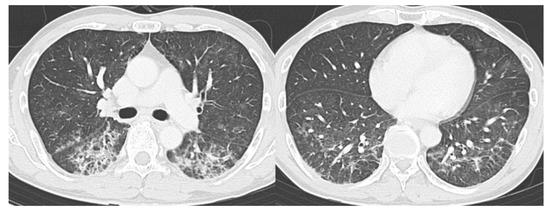

- CO-RADS 3 means CT findings equivocal for pulmonary involvement of COVID-19 that can also be seen in other types of viral pneumonia or non-infectious etiologies. Findings include perihilar ground-glass, homogenous extensive ground-glass with or without sparing of some secondary pulmonary lobules, or ground-glass together with smooth interlobular septal thickening with or without pleural effusion in the absence of other typical CT findings.